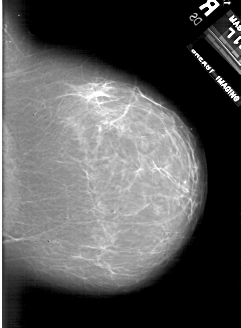

A_1818_1.RIGHT_CC

RIGHT_CC LINES 6226 PIXELS_PER_LINE 4561 BITS_PER_PIXEL 12 RESOLUTION 43.5 NON_OVERLAY